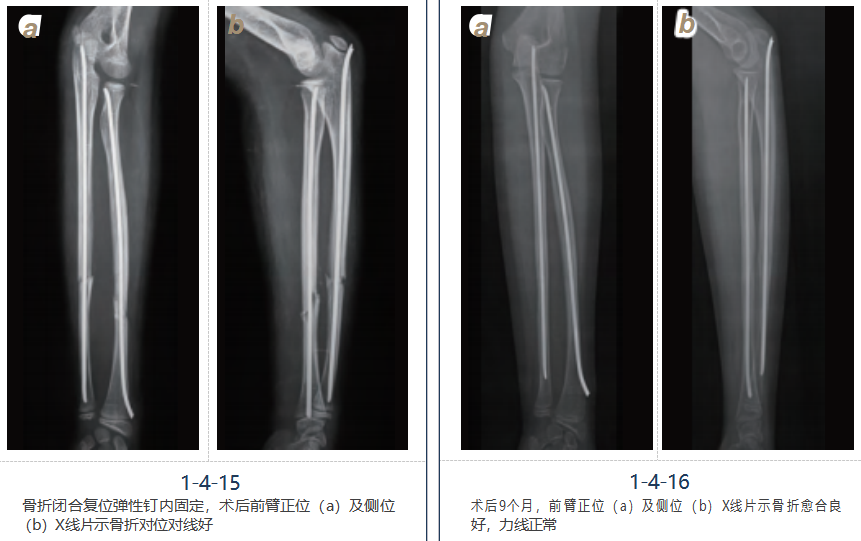

病例二

女,10岁,摔伤致左前臂肿胀、压痛、畸形、活动受限,诊断为左尺桡骨骨折,行左尺 桡骨骨折闭合复位弹性钉内固定术,术后恢复良好(图1-4-14~16)。